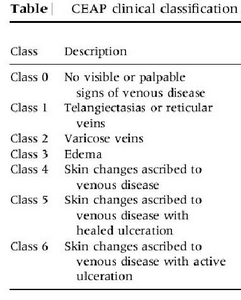

(2) CEAP